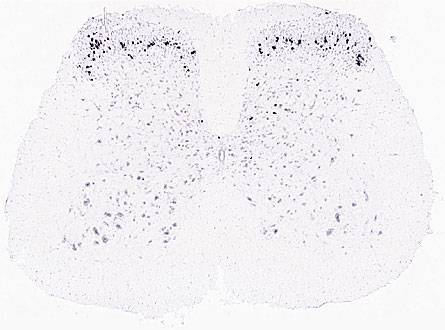

The Allen Institute for Brain Science in Seattle launched its online atlas of the mouse spinal cord July 16. The initial release includes 4,000 sets of digital images of spinal cords from adult and juvenile mice. The pictures show where in the spinal cord 2,000 different genes are active. By the end of the year, data for 20,000 genes will be available, says Allan Jones, chief scientific officer for the nonprofit research organization.

When and where genes are active in the spinal cord guides development. It can also make a difference in passing along signals from brain to body. The Allen Institute’s atlas won’t contain information about what all of the genes are doing in the spinal cord. But the atlas will give scientists a starting place for investigations of the various gene functions.